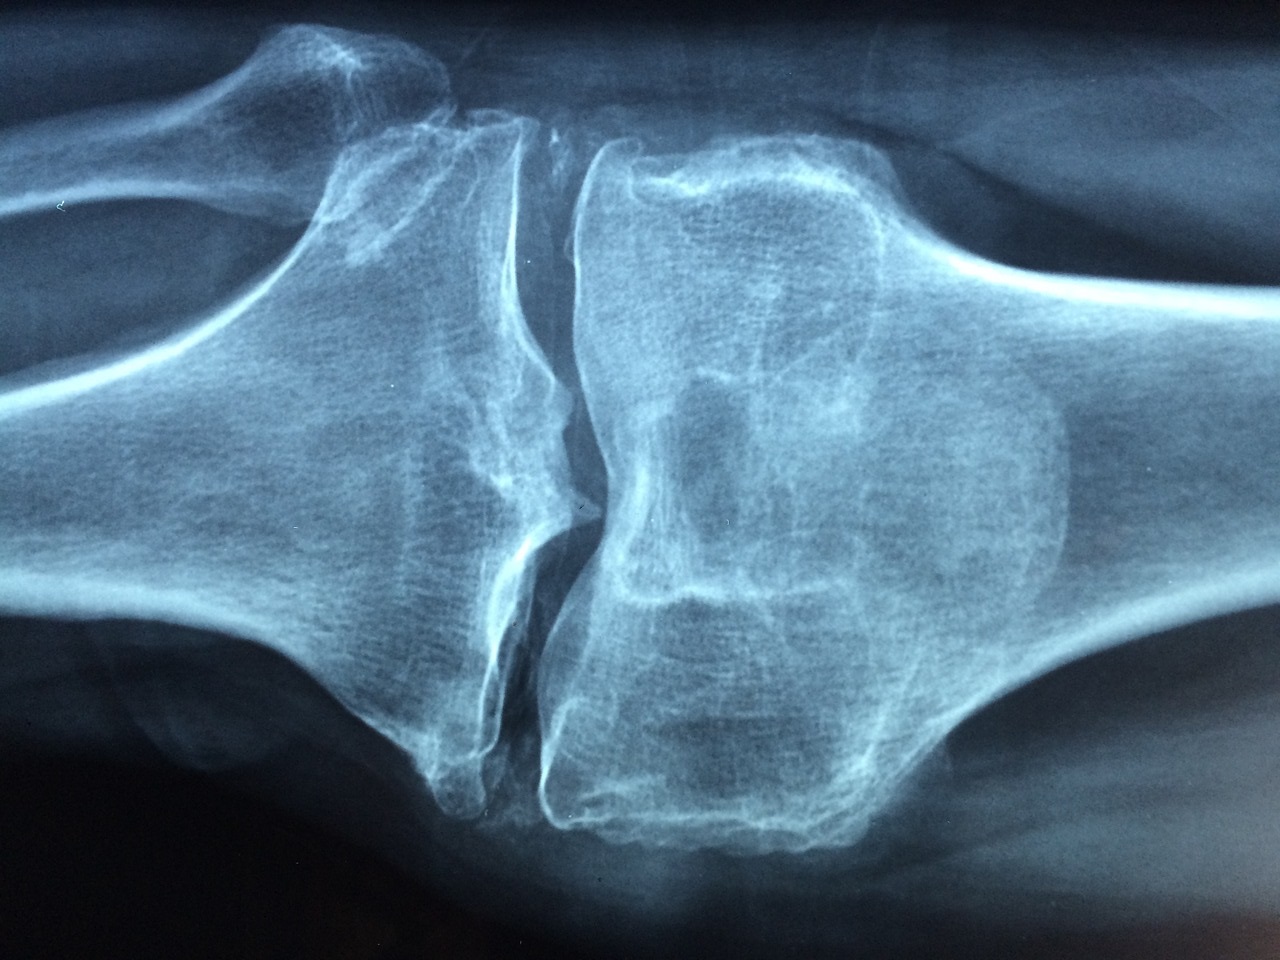

La densitometria ossea è un esame fondamentale per la diagnosi di osteoporosi o di altre patologie che coinvolgono l’apparato scheletrico. Chiamata anche MOC (Mineralometria Ossea Computerizzata), consente di rilevare la densità minerale delle ossa e quindi comprenderne lo stato di usura. Anche se come vedremo può rivelarsi utile in diversi contesti, la densitometria ossea viene nella maggior parte dei casi prescritta quando sussite il dubbio che il paziente possa soffrire di osteoporosi. Questa patologia infatti comporta una progressiva riduzione del contenuto minerale delle ossa che vanno incontro ad un deterioramento graduale e ad un sempre maggior rischio di fratture.

La densitometria ossea viene effettuata mediante apparecchiature in grado di emettere delle radiazioni ionizzanti e di consentire l’osservazione della struttura ossea. A seconda della struttura, possono essere utilizzati strumenti differenti ma al giorno d’oggi la DEXA è quella più diffusa e anche maggiormente sicura. E’ bene precisare sin da subito che la quantità di raggi x che viene emessa con la densitometria ossea è davvero minima, quindi il paziente non è esposto ad alcun rischio.